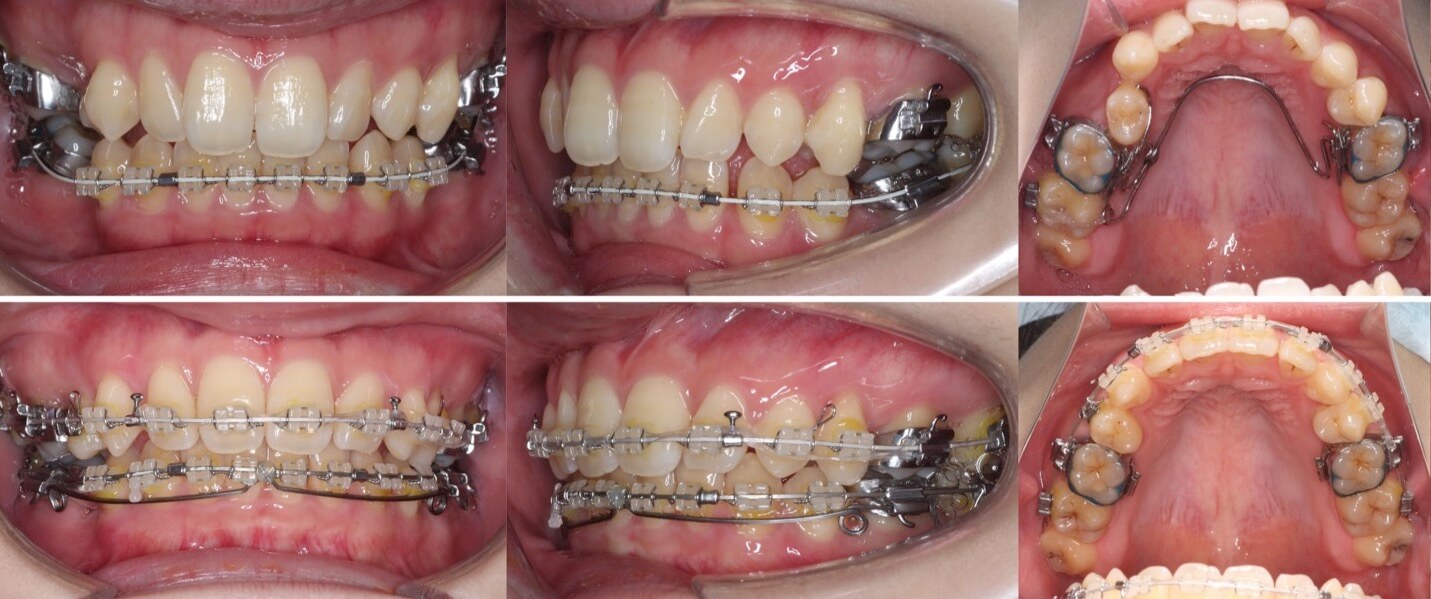

30代女性・大臼歯抜歯済・上6番欠損

<症例概要>

主訴:出っ歯

年齢・性別:30代女性

症状:左上6番欠損・上顎前突・過蓋咬合

治療方針:抜歯空隙閉鎖

抜歯:右上5番(計1本)

治療装置:唇側矯正装置

固定装置:歯科矯正用アンカースクリュー

治療期間:3年6か月

リテーナー:上下フィックスタイプ+プレートタイプタイプ

治療費用:968,000(税込)

代表的副作用:痛み・治療後の後戻り・歯根吸収・歯髄壊死・歯肉退縮

虫歯で左上大臼歯(6番)を抜歯してしまっている状態です。抜歯部位はブリッジ治療を検討していたのですが、矯正治療もしたいということで当院に来られました。6番の抜歯あとは、ふだん出っ歯の矯正治療抜歯をする小臼歯の1.5倍近くの空隙があります。よって歯科矯正用アンカースクリューを使用してゆっくりとつめていきました。治療期間も1.5倍かかりましたが、しっかりと隙間と閉じることができました。